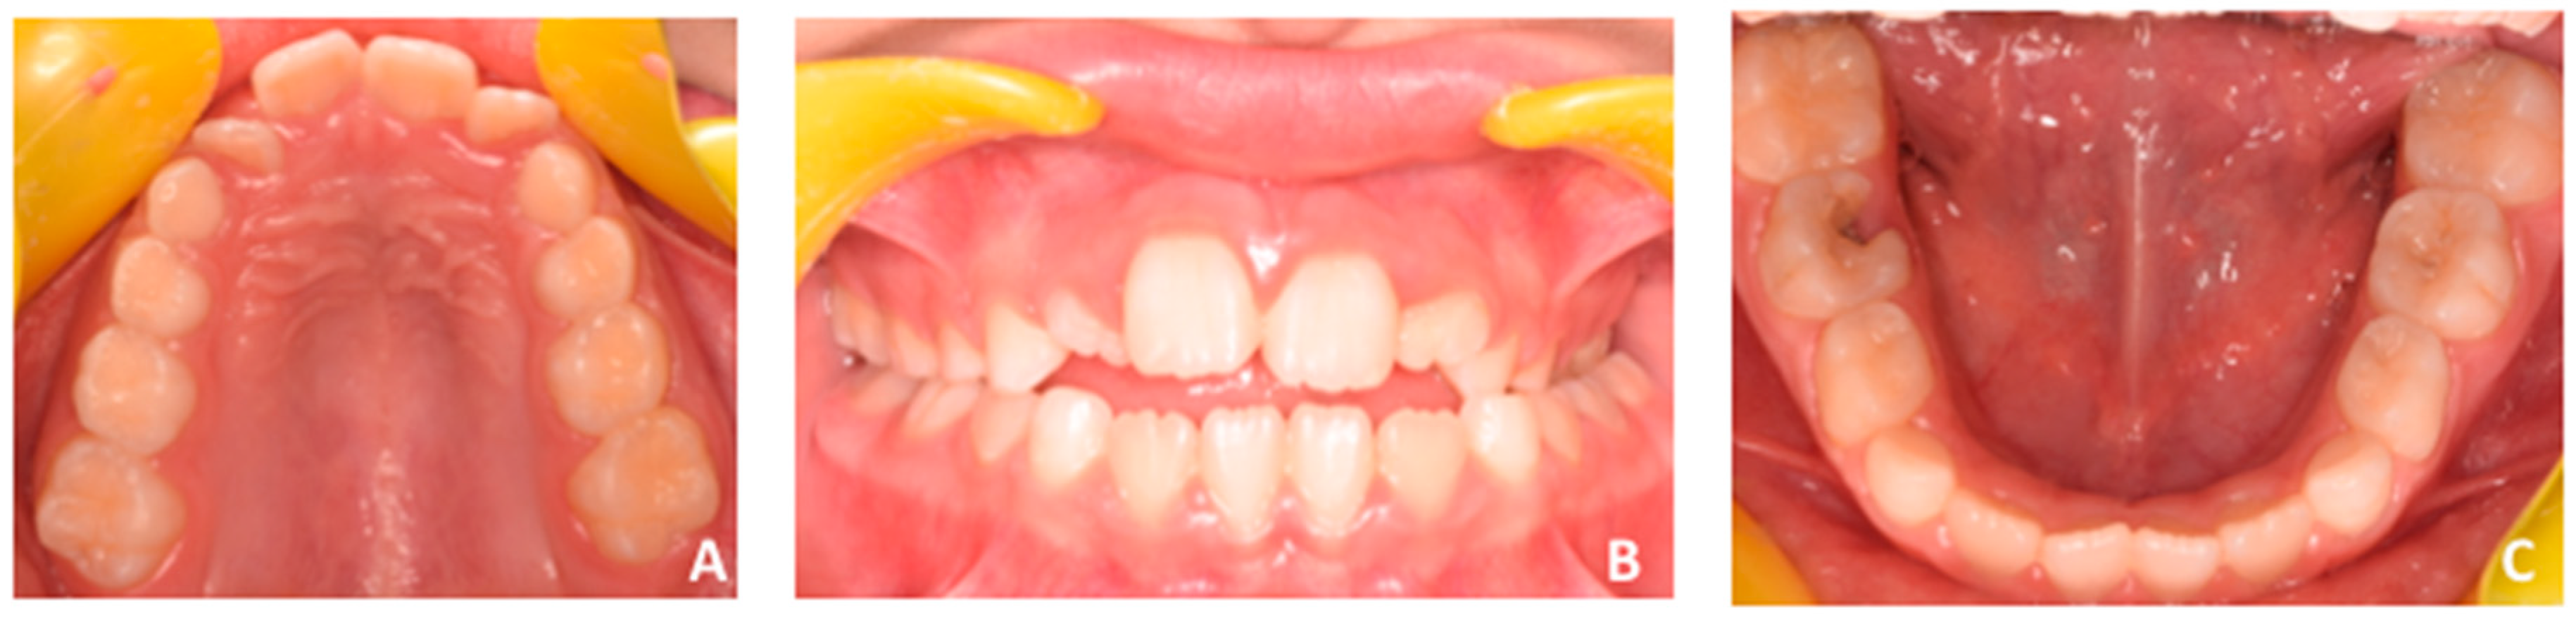

Facial examination revealed a eugnatic jaw growing pattern, slight retrusive profile with opened naso-labial angle, and labial competence (Figure 1). Intra-oral clinical examination, recorded with intra-oral photographs (Figure 2), showed early mixed dentition, a 5 mm anterior openbite, and posterior crossbite at the left side with small loss of coincidence between maxillary and mandibular midlines due to a slight shift of the mandible toward the crossbite side. Both the upper and lower midlines are coincident with the center of maxillary and mandibular arches. Functional examination revealed the presence of infant swallowing pattern with the tongue keeping an anterior position in an attempt to close the anterior space during swallowing or feeding.

Figure 2.

(A–C) Intra-oral examination. See the presence of anterior openbite (A). Additionally, posterior crossbite is present at the left side (B) with loss of coincidence between maxillary and mandibular midlines due to a slight shift of the mandible toward the crossbite side (left side). Both the upper and lower midlines are coincident with the center of maxillary (A) and mandibular (B) arches.